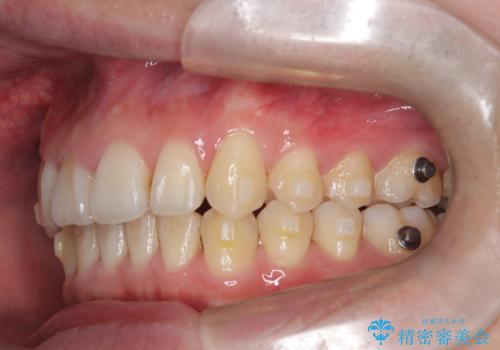

- 前歯が出ていることを主訴に来院されました。

歯列の幅が狭かったため、横に広げながらスペースを作り、叢生の改善を行いました。

左側の犬歯関係も治療前より良い状態で治療を完了することができました。

今回は臼歯部の遠心移動を行うために2級ゴムを使用しています。